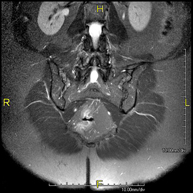

- Neuroradiology

- Brain MRI (cranial)

This non-invasive diagnostic procedure uses an electromagnetic field and radio waves (from a transmitter and receiver) to acquire high-definition anatomical images of the brain. It is a radiation-free procedure. Indicated for: vascular problems, memory loss, epilepsy, headache, malformations, suspected tumour, meningitis.